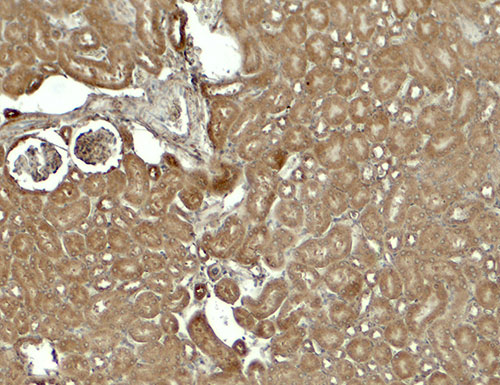

Immunohistochemistry of SESTRIN2 in mouse kidney tissue with SESTRIN2 antibody at 5 μg/ml.